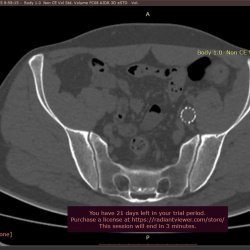

Пациентка 38 лет. Жалобы на дискомфорт в эпигастрии.